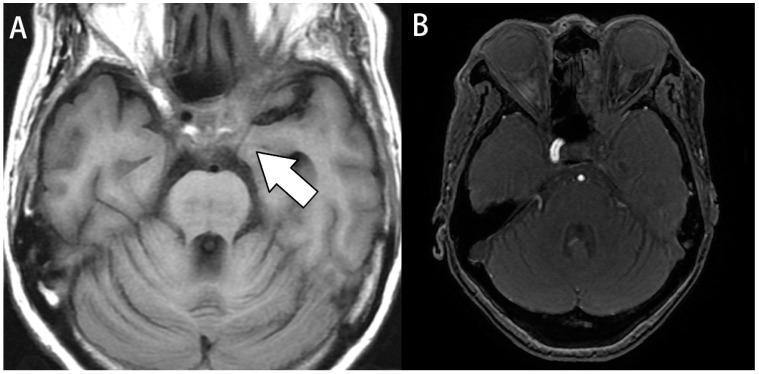

Various diseases involving the cavernous sinus can cause a condition called cavernous sinus syndrome (CSS), which is characterized by ophthalmoplegia or sensory deficits over the face resulting from the compression effect of internal structure. While tumor compression is the most reported cause of CSS, statistical data on CSS caused by infections are limited. Its risk factors, treatment methods, and clinical outcomes are not well-documented. In this retrospective study, we reviewed the data of patients admitted to a tertiary medical center from 2015 to 2022 with a diagnosis of acute and chronic sinusitis and at least one diagnostic code for CSS symptoms. We manually reviewed whether patients were involved in two or more of the following cranial nerves (CN): CN III, CN IV, CN V, or CN VI, or at least one of these nerves with a neuroimaging-confirmed lesion in the cavernous sinus. Nine patients were diagnosed with rhinosinusitis-related CSS. The most common comorbidity was type 2 diabetes, and the most common clinical manifestations were diplopia and blurred vision. The sphenoid sinus was the most affected sinus. One patient expired due to a severe brain abscess infection without surgery. The remaining patients underwent functional endoscopic sinus surgery, and 50% of the pathology reports indicated fungal infections. spp. was the most cultured bacteria, and Amoxycillin/Clavulanate was the most used antibiotic. Only four patients had total recovery during the follow-up one year later. CSS is a rare but serious complication of rhinosinusitis. Patients with diabetes and the elderly may be at a higher risk for this complication. Even after treatment, some patients may still have neurological symptoms.

各种累及海绵窦的疾病可导致一种称为海绵窦综合征(CSS)的病症,其特征为眼肌麻痹或因内部结构受压而导致面部感觉缺陷。虽然肿瘤压迫是CSS最常见的病因报道,但关于感染所致CSS的统计数据有限。其危险因素、治疗方法及临床结果尚无充分记录。在这项回顾性研究中,我们回顾了2015年至2022年入住一家三级医疗中心、诊断为急慢性鼻窦炎且至少有一个CSS症状诊断编码的患者数据。我们人工检查患者是否累及以下两条或更多颅神经(CN):CN III、CN IV、CN V或CN VI,或这些神经中至少一条在海绵窦有神经影像学证实的病变。9例患者被诊断为鼻窦炎相关性CSS。最常见的合并症是2型糖尿病,最常见的临床表现是复视和视力模糊。蝶窦是受累最严重的鼻窦。1例患者因严重脑脓肿感染未手术而死亡。其余患者接受了功能性内镜鼻窦手术,50%的病理报告显示为真菌感染。spp.是培养最多的细菌,阿莫西林/克拉维酸是最常用的抗生素。在随访一年后,只有4例患者完全康复。CSS是鼻窦炎一种罕见但严重的并发症。糖尿病患者和老年人可能发生这种并发症的风险更高。即使经过治疗,一些患者可能仍有神经症状。